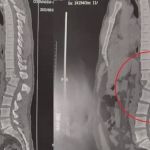

Raio-X mostra lesão na coluna do homem atingido por aparelho de academia; veja

Regilânio Inácio teve uma lesão gravíssima e tem menos de 1% de chance de voltar a andar; academia criticou divulgação 'inadequada' dos vídeos do acidente